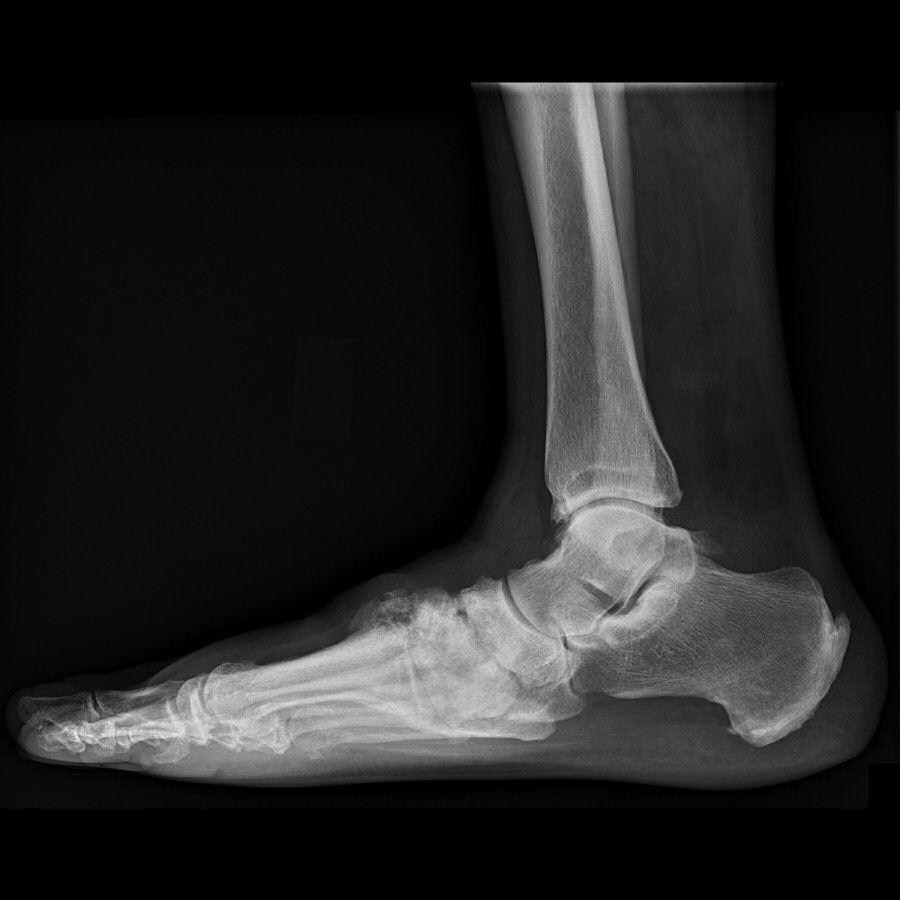

Obehandlad charcotfot, patienten noterade formförändring i fot ca 1 månad innan undersökning